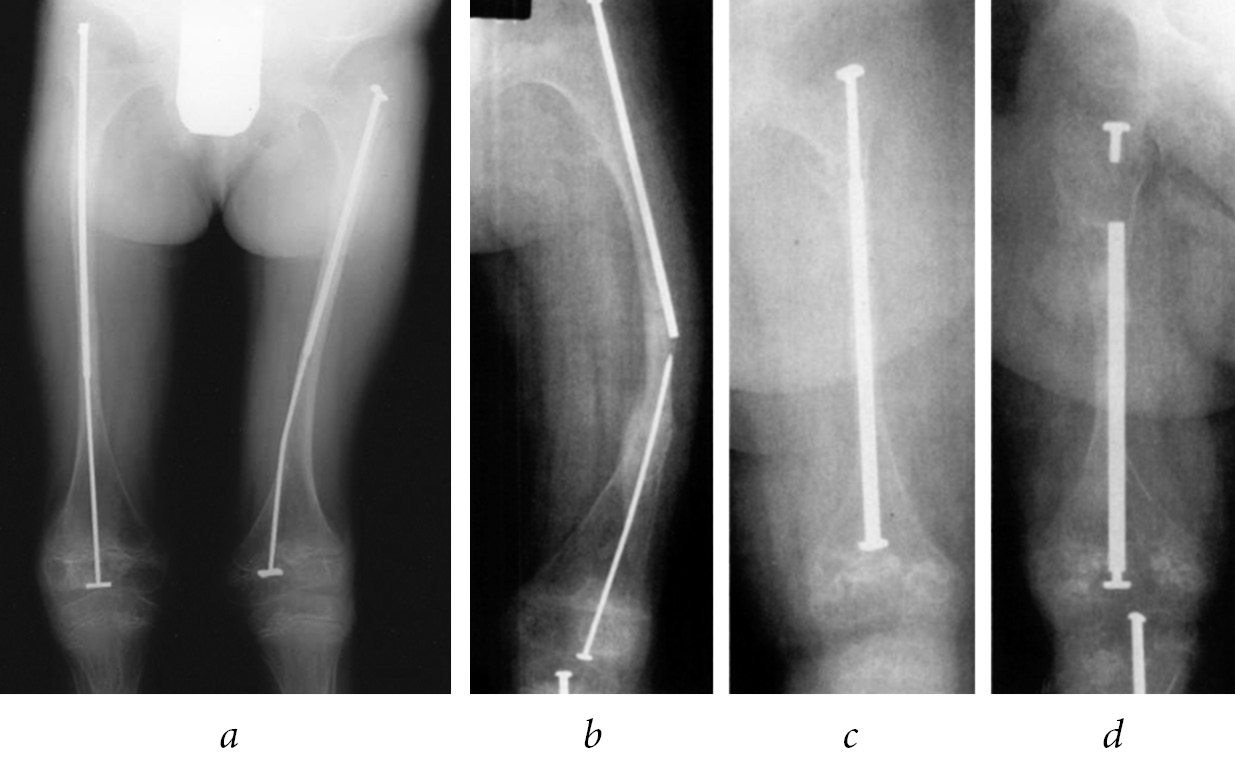

As a result of BP action, the bone remodeling process slows down, leading to increased bone mineralization. The radiographs of long bones show a horizontal line of sclerosis above the growth zone. The number of lines corresponds to the number of BP regimens (Fig. 2). The risk of fracture increases in this zone.

Fig. 2. Lines of bone sclerosis after treatment with bisphosphonates